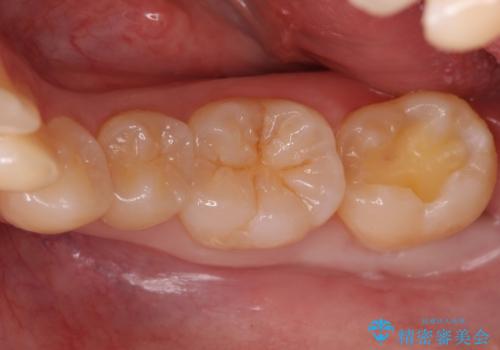

奥歯の虫歯 セラミックインレーでの治療

- 下の奥歯の黒ずみが気になるとのことで来院されました。

検査の結果咬む面に虫歯があることがわかりました。

削る前は小さな虫歯に見えますが、歯の中で進行しつつある虫歯でした。

虫歯が大きくなると必要な治療が増えてえしまうため早期発見、早期治療を行うことが大事になってきます。